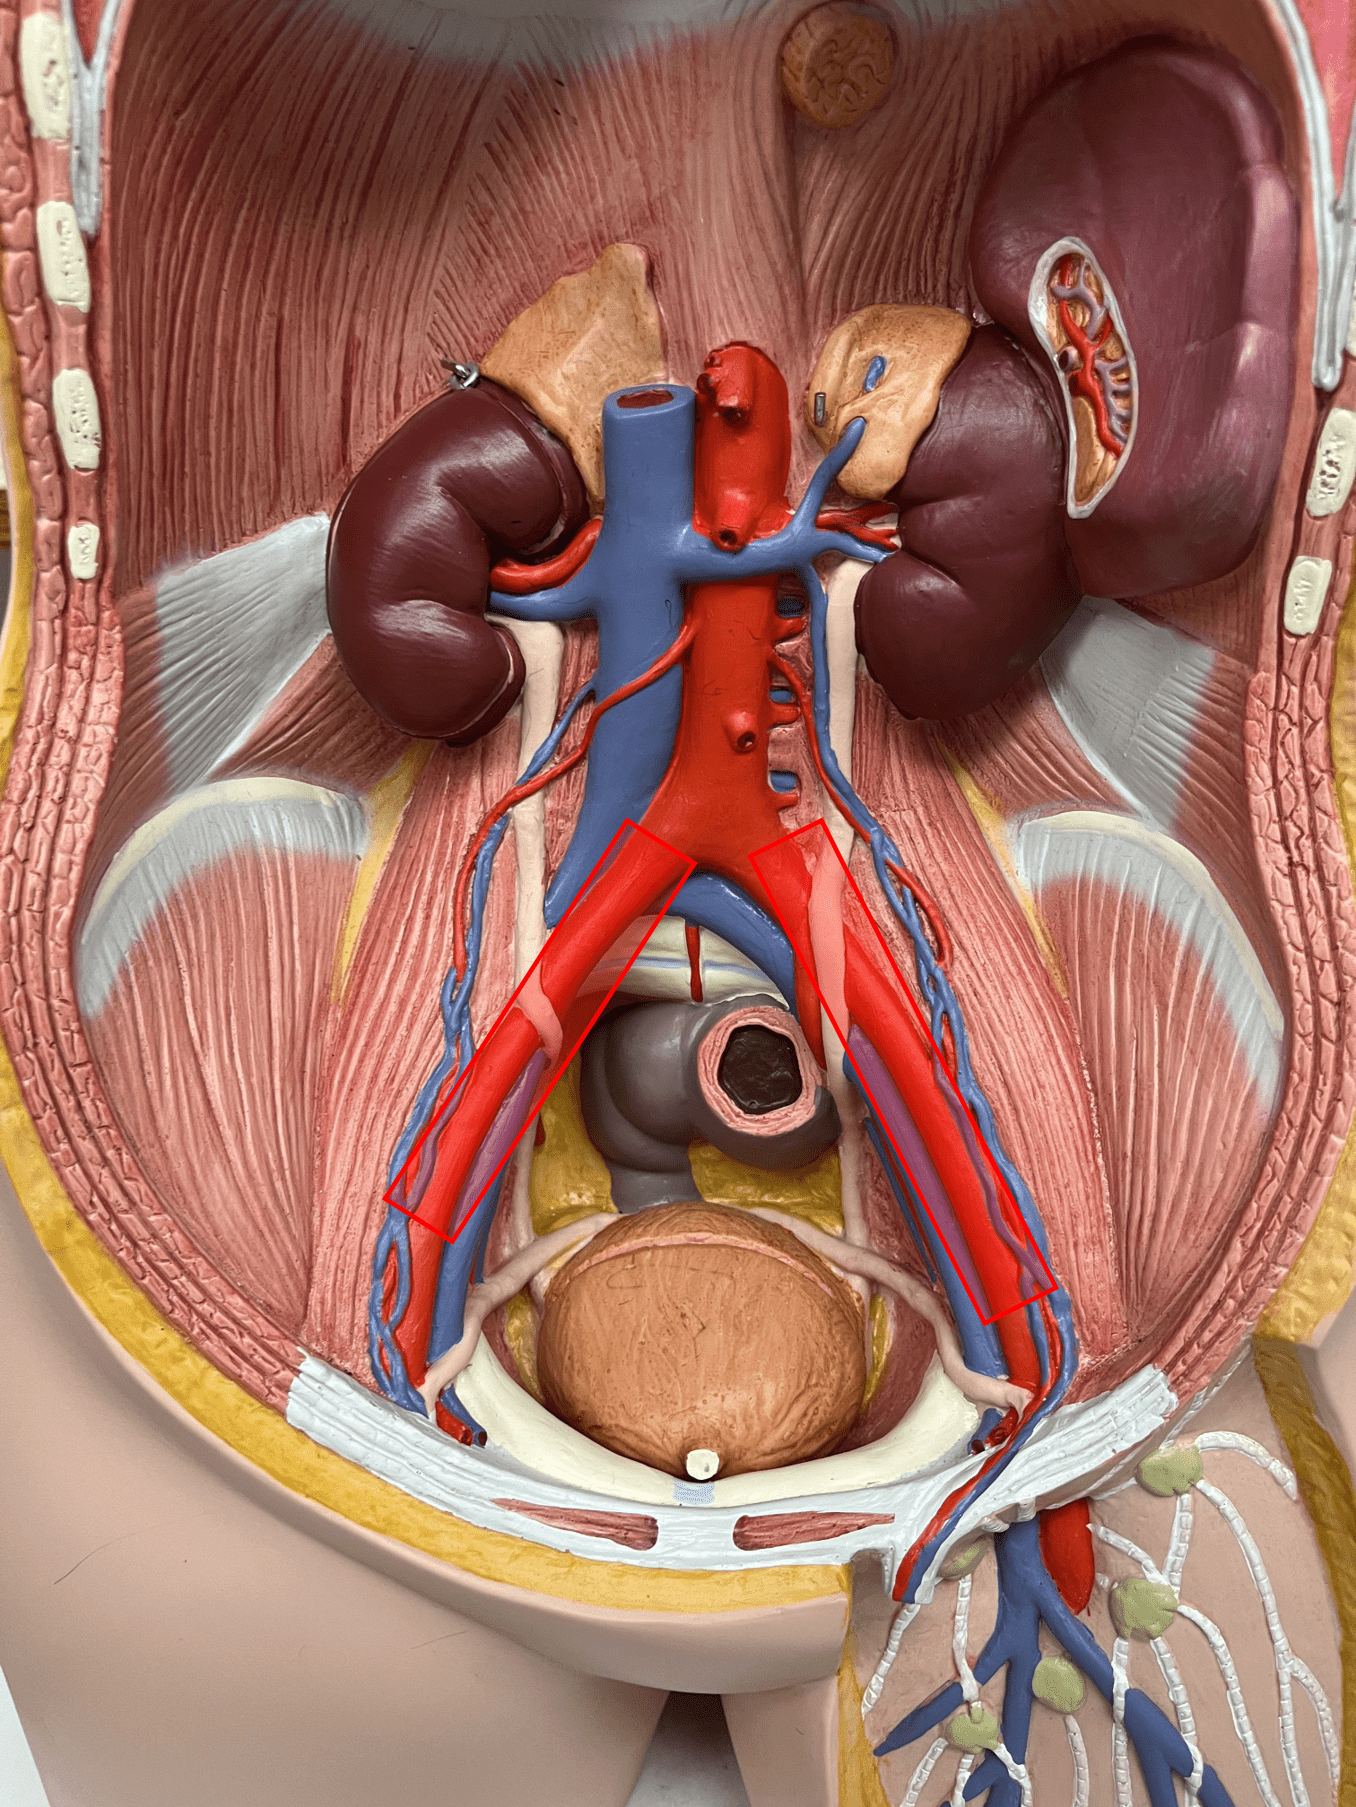

11

New cards

endothelium

• Originates from the brachiocephalic trunk (R.) or the aortic arch (L.).

• Supplies the head and neck through its branches.

• Originates from the brachiocephalic trunk (R.) or the aortic arch (L.).

• Supplies the head and neck through its branches.